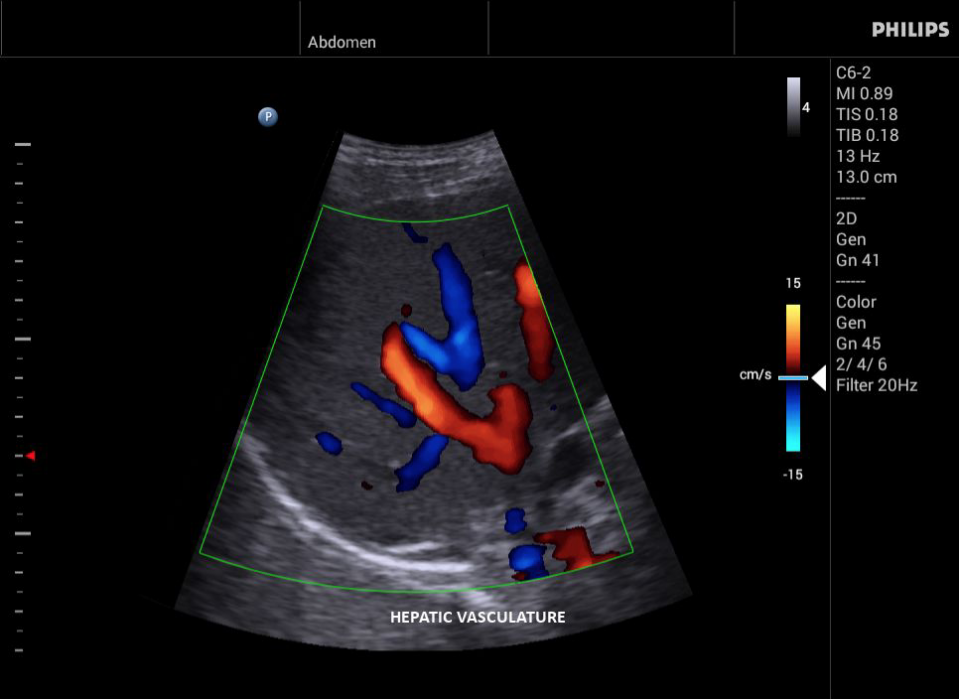

• Цветное допплеровское картирование

• Направленный энергетический допплеровский режим: Дополнительно к возможностям визуализации сосудов в стандартном энергетическом режиме добавляется информация о направлении. Этот режим полезен для визуализации мелких сосудов в качестве замены цветного допплеровского картирования.

• Конвексный УЗИ датчик Philips С6-2